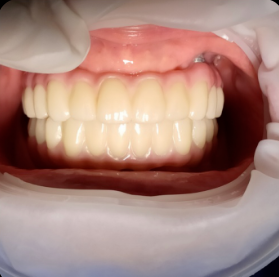

한눈에 보는 치료법 비교

특징 디지털 풀아치 전체 임플란트 전통 틀니

씹는 힘 우수 (자연치 80%) 최우수 (90~100%) 미흡 (20~30%)

뼈 이식 거의 불필요 필요한 경우 많음 해당 없음

편안함 고정식, 이물감 없음 고정식, 내 치아 같음 탈착식, 이물감 있음

치료 기간 단기간 (약 2~3개월) 장기(6개월~1년) 비교적 빠름

장기 안정성 매우 높음 (10년 후 93% 이상) 매우 높음 재제작 필요 (5~7년 주기)

전체 비용 높음 매우 높음 낮음(중)